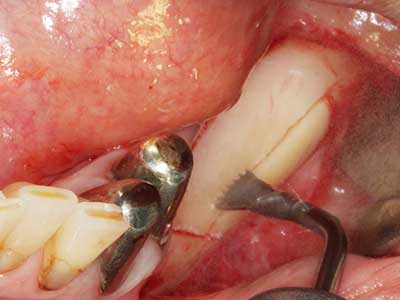

Marginal periodontal diseases are the main reason for extractions in advanced age. These diseases are primarily caused by bacterial colonization of the gingival pocket, which causes inflammation followed by loss of the periodontium. The formation of subgingival biofilms and concrements is a significant aetiological factor for marginal bone atrophy, so their removal is an important part of the treatment (Drisko 2014, Plessas 2014).

Initial and surgical treatment phases are differentiated in the treatment of marginal periodontitis. In addition to instruction in oral hygiene and motivating patients, both phases should include adequate cleaning of the root surface. In the regenerative setting an open access is generally preferred. The root surface can be cleaned by piezo surgery using special attachments, where instruments with different curvatures are used to reach areas that are difficult to access, such as furcations. The integrated irrigation in the system flushes the detached concrements and bacteria out of the pocket. Specialized systems such as the Piezomed also include application feedback to minimize the ablation of hard dental substance. The greater the pressure on the periodontal attachment the greater the reduction in the amount of ablation.